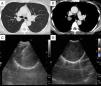

Case PresentationA 47-year-old woman was referred to our hospital for diagnostic testing of a lung tumor. She had undergone right thyroid lobectomy for papillary thyroid adenocarcinoma two years previously. The patient was afebrile with no palpable lymph nodes, and her vital signs and pulmonary auscultation were normal. Biochemistry and hematology tests were unremarkable. Chest X-ray showed a 2-cm nodule in the upper right lung field. Chest computed tomography (CT) (Fig. 1A and B) revealed a round, well-defined 2.4-cm nodule in S2, adjacent to the right upper lobe bronchus. A sub-mucosal lesion and almost complete occlusion of the right upper lobe bronchus were identified on bronchscopy. EBUS showed a well-defined hypoechoic tumor, with an echogenic capsule and posterior acoustic enhancement (Fig. 1C and D). Nerve continuity was not detected. EBUS-TBNA was performed, as a histological diagnosis may have been difficult to obtain with transbronchial biopsy. The EBUS-TBNA sample showed hypercellular areas with proliferation of fusiform cells and hypocellular areas (Fig. 2A and B). Immunostaining for S-100 was positive (Fig. 2C), and a diagnosis of schwannoma was confirmed. Rapid on-site cytologic evaluation was not performed. The patient underwent tumorectomy due to the possibility of obstructive pneumonia. Pathological examination of the surgical specimen further supported the diagnosis of schwannoma.

On ultrasound, schwannoma is a well-defined hypoechogenic tumor.5 In some cases an echogenic capsule, posterior acoustic enhancement and nerve continuity are also detected.5 However, these characteristics are typical of schwannoma located in the limbs or near the surface of the body. As far as we know, identification of an intrapulmonary schwannoma with endobronchial ultrasound has not hitherto been described. In our case, it showed a well-defined hypoechogenic encapsulated mass, with posterior acoustic enhancement, although nerve continuity was not detected. These characteristics could be useful for diagnosing a tumor of nerve origin in the lung.